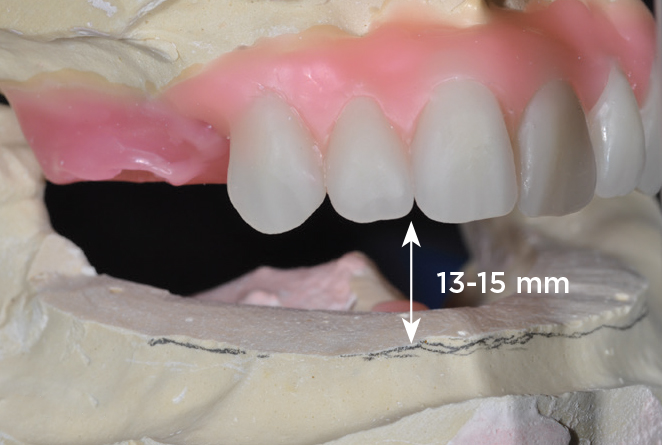

An important advantage of this approach is the ability to simulate bone reduction on the models and verify the presence of 15 mm to 17 mm and 13 mm to 15 mm of required inter-occlusal space for maxillary and mandibular restorations, respectively. This creates a platform for a diagnostic wax-up of the proposed dental rehabilitation and fabrication of wax prosthesis try-ins when necessary. Finally, a modified All-on-4 provisional prosthesis surgical and restorative guide developed by the authors for restoration-driven surgery and simplified restorative procedures is fabricated (Figure 2 through Figure 8).

Fig 5. Bone reduction model surgery performed in mandibular arch to create 13 mm to 15 mm of inter-occlusal space required for the mandibular All-on-4 provisional restoration.

Figure 5